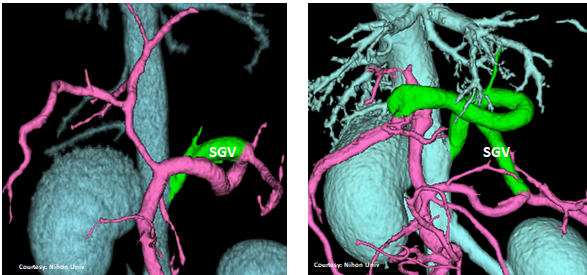

Does the SHORT GASTRIC VEIN (SGV) contribute blood to the shunt?

slide12

slide15